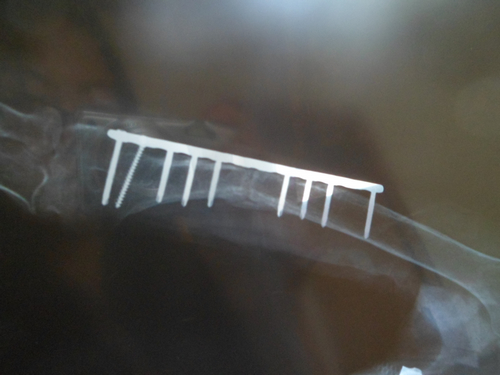

鋼釘明顯打在骨縫里,且斷裂兩顆

????“這要是不檢查還不知道,我看到給我父親拍的X光片,竟然有一根鋼釘打進了骨頭斷裂的接縫處?!壁w女士氣憤地向記者說道,她找到當時的主治醫生想問個究竟,結果醫院表示胳膊沒有愈合和鋼釘沒有關系。趙女士拿出當時給她父親拍的X光片,對記者說,“你看這是第一次手術后去醫院檢查時拍的片子,胳膊上的鋼板總共釘了9顆鋼釘,有兩顆已經斷了,還有一顆明顯是打進骨頭的接縫的地方了?!?/p>